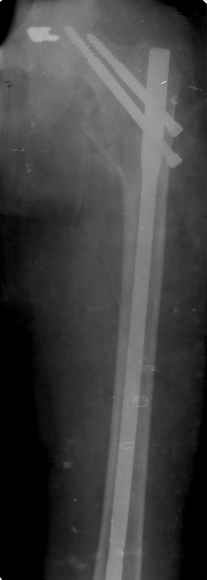

Спасибо за все ответы и комментарии по этому вопросу. Неделю назад мы прооперировали пациентку. Представляем ее снимки.

Получилось очень красиво! У меня возникло два вопроса: 1) проводилось ли выскабливание полости; 2) проводилась ли пластика?

Уважаемый Азат! Ответ на оба Ваши вопроса - отрицательный.